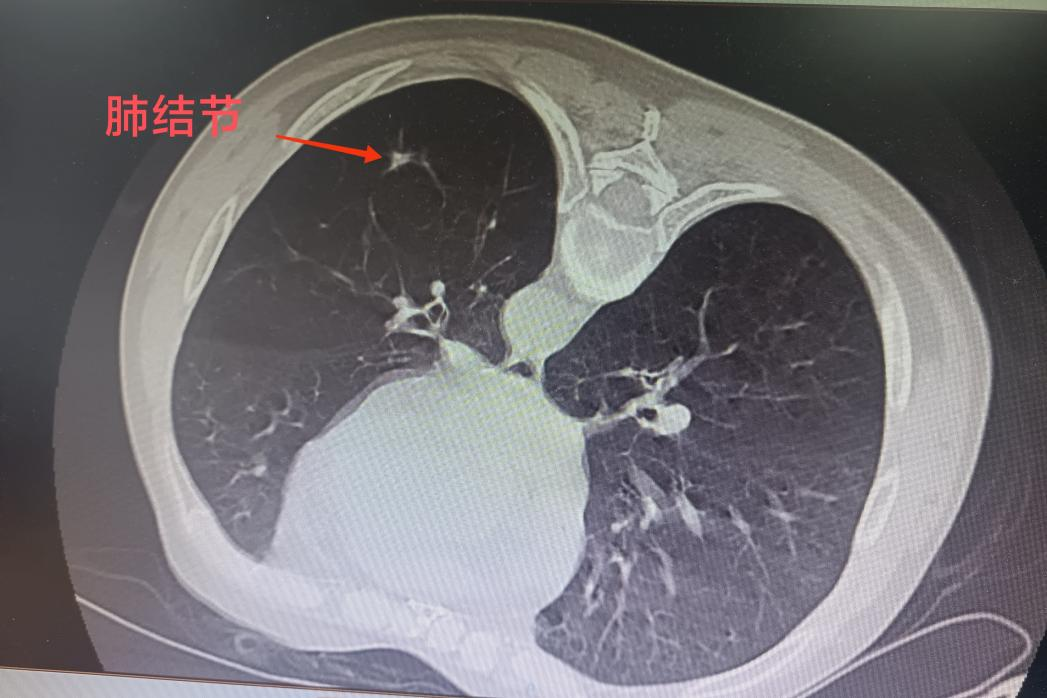

微波射頻針精準(zhǔn)定位肺部結(jié)節(jié)